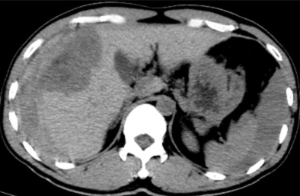

据悉,患者既往有多年乙型肝炎病史,突发右上腹剧烈疼痛入院。患者入院时血压70/40mmHg,心率110次/分,全腹压痛。血常规血红蛋白87g/L,甲胎蛋白>1210 ng/ml。腹部B超检查及CT平扫检查示“肝肿瘤并出血,腹腔积血积液”。